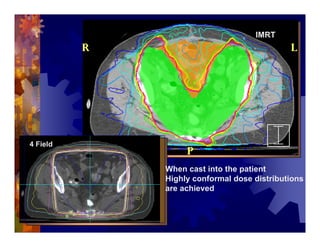

1) Intensity modulated radiation therapy (IMRT) is a technique that uses computer software to conform the radiation dose to the shape of the tumor, reducing dose to surrounding normal tissues and decreasing toxicity. 2) Numerous studies have shown IMRT provides better sparing of the small bowel, bladder, and rectum compared to conventional radiation for gynecologic cancers. 3) IMRT may allow dose escalation to high risk sites or involved nodes while maintaining normal tissue doses. Some studies have also investigated using IMRT as an alternative to brachytherapy boosts. 4) Clinical studies suggest IMRT results in low rates of acute gastrointestinal and genitourinary toxicity compared to conventional radiation for